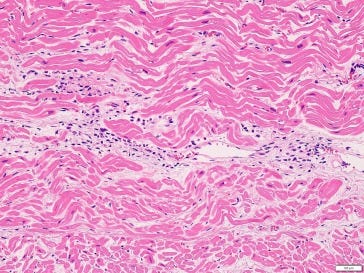

‘In the assessment of adverse events, myocarditis was found to be the cause of death in two cases (cases 40, 54) (Fig. 1,Fig. 2.), and causal relationships to vaccination were possible. Another case showed myocarditis (case 4) while a competing cause of death (pre-existing ischemic heart disease) was found.